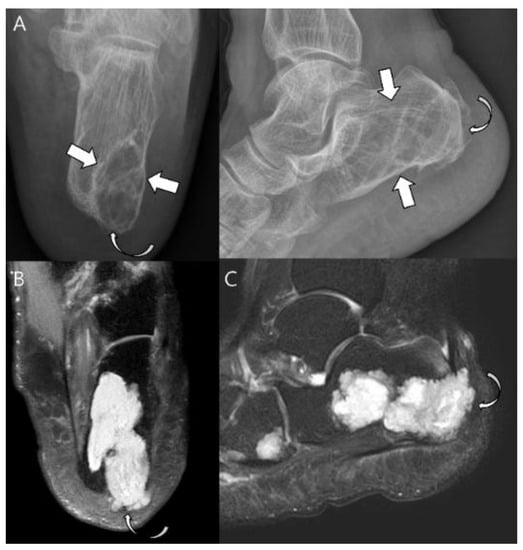

- Collins, M.S.; Koyama, T.; Swee, R.G.; Inwards, C.Y. Clear cell chondrosarcoma: Radiographic, computed tomographic, and magnetic resonance findings in 34 patients with pathologic correlation. Skelet. Radiol. 2003, 32, 687–694. [Google Scholar] [CrossRef]

- Kumar, R.; David, R.; Cierney, G., 3rd. Clear cell chondrosarcoma. Radiology 1985, 154, 45–48. [Google Scholar] [CrossRef]

- Bagley, L.; Kneeland, J.B.; Dalinka, M.K.; Bullough, P.; Brooks, J. Unusual behavior of clear cell chondrosarcoma. Skelet. Radiol. 1993, 22, 279–282. [Google Scholar] [CrossRef]

- PPresent, D.; Bacchini, P.; Pignatti, G.; Picci, P.; Bertoni, F.; Campanacci, M. Clear cell chondrosarcoma of bone. Skelet. Radiol. 1991, 20, 187–191. [Google Scholar] [CrossRef] [PubMed]